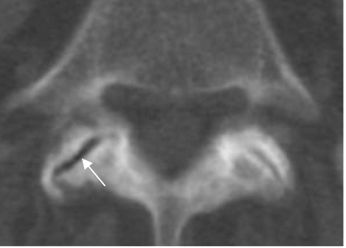

Fig 66. Articulaciones intervertebrales.

A: RM axial en T1 y B: RM axial en T2. Cambios degenerativos incipientes en la articulación interfacetaria izquierda, con presencia de líquido, hipointenso en T1 e hiperintenso en T2.